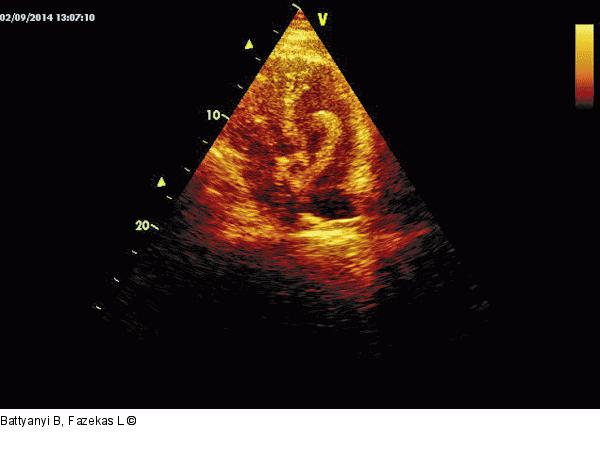

Abbildung 2: Apikaler Vierkammerblick Apikaler Vierkammerblick: Lange echoreiche, anscheinlich am Vorhofseptum fixierte Masse prolabiert in die rechte und (weniger sichtbar) in die linke Kammer. |

Apikaler Vierkammerblick: Lange echoreiche, anscheinlich am Vorhofseptum fixierte Masse prolabiert in die rechte und (weniger sichtbar) in die linke Kammer. |